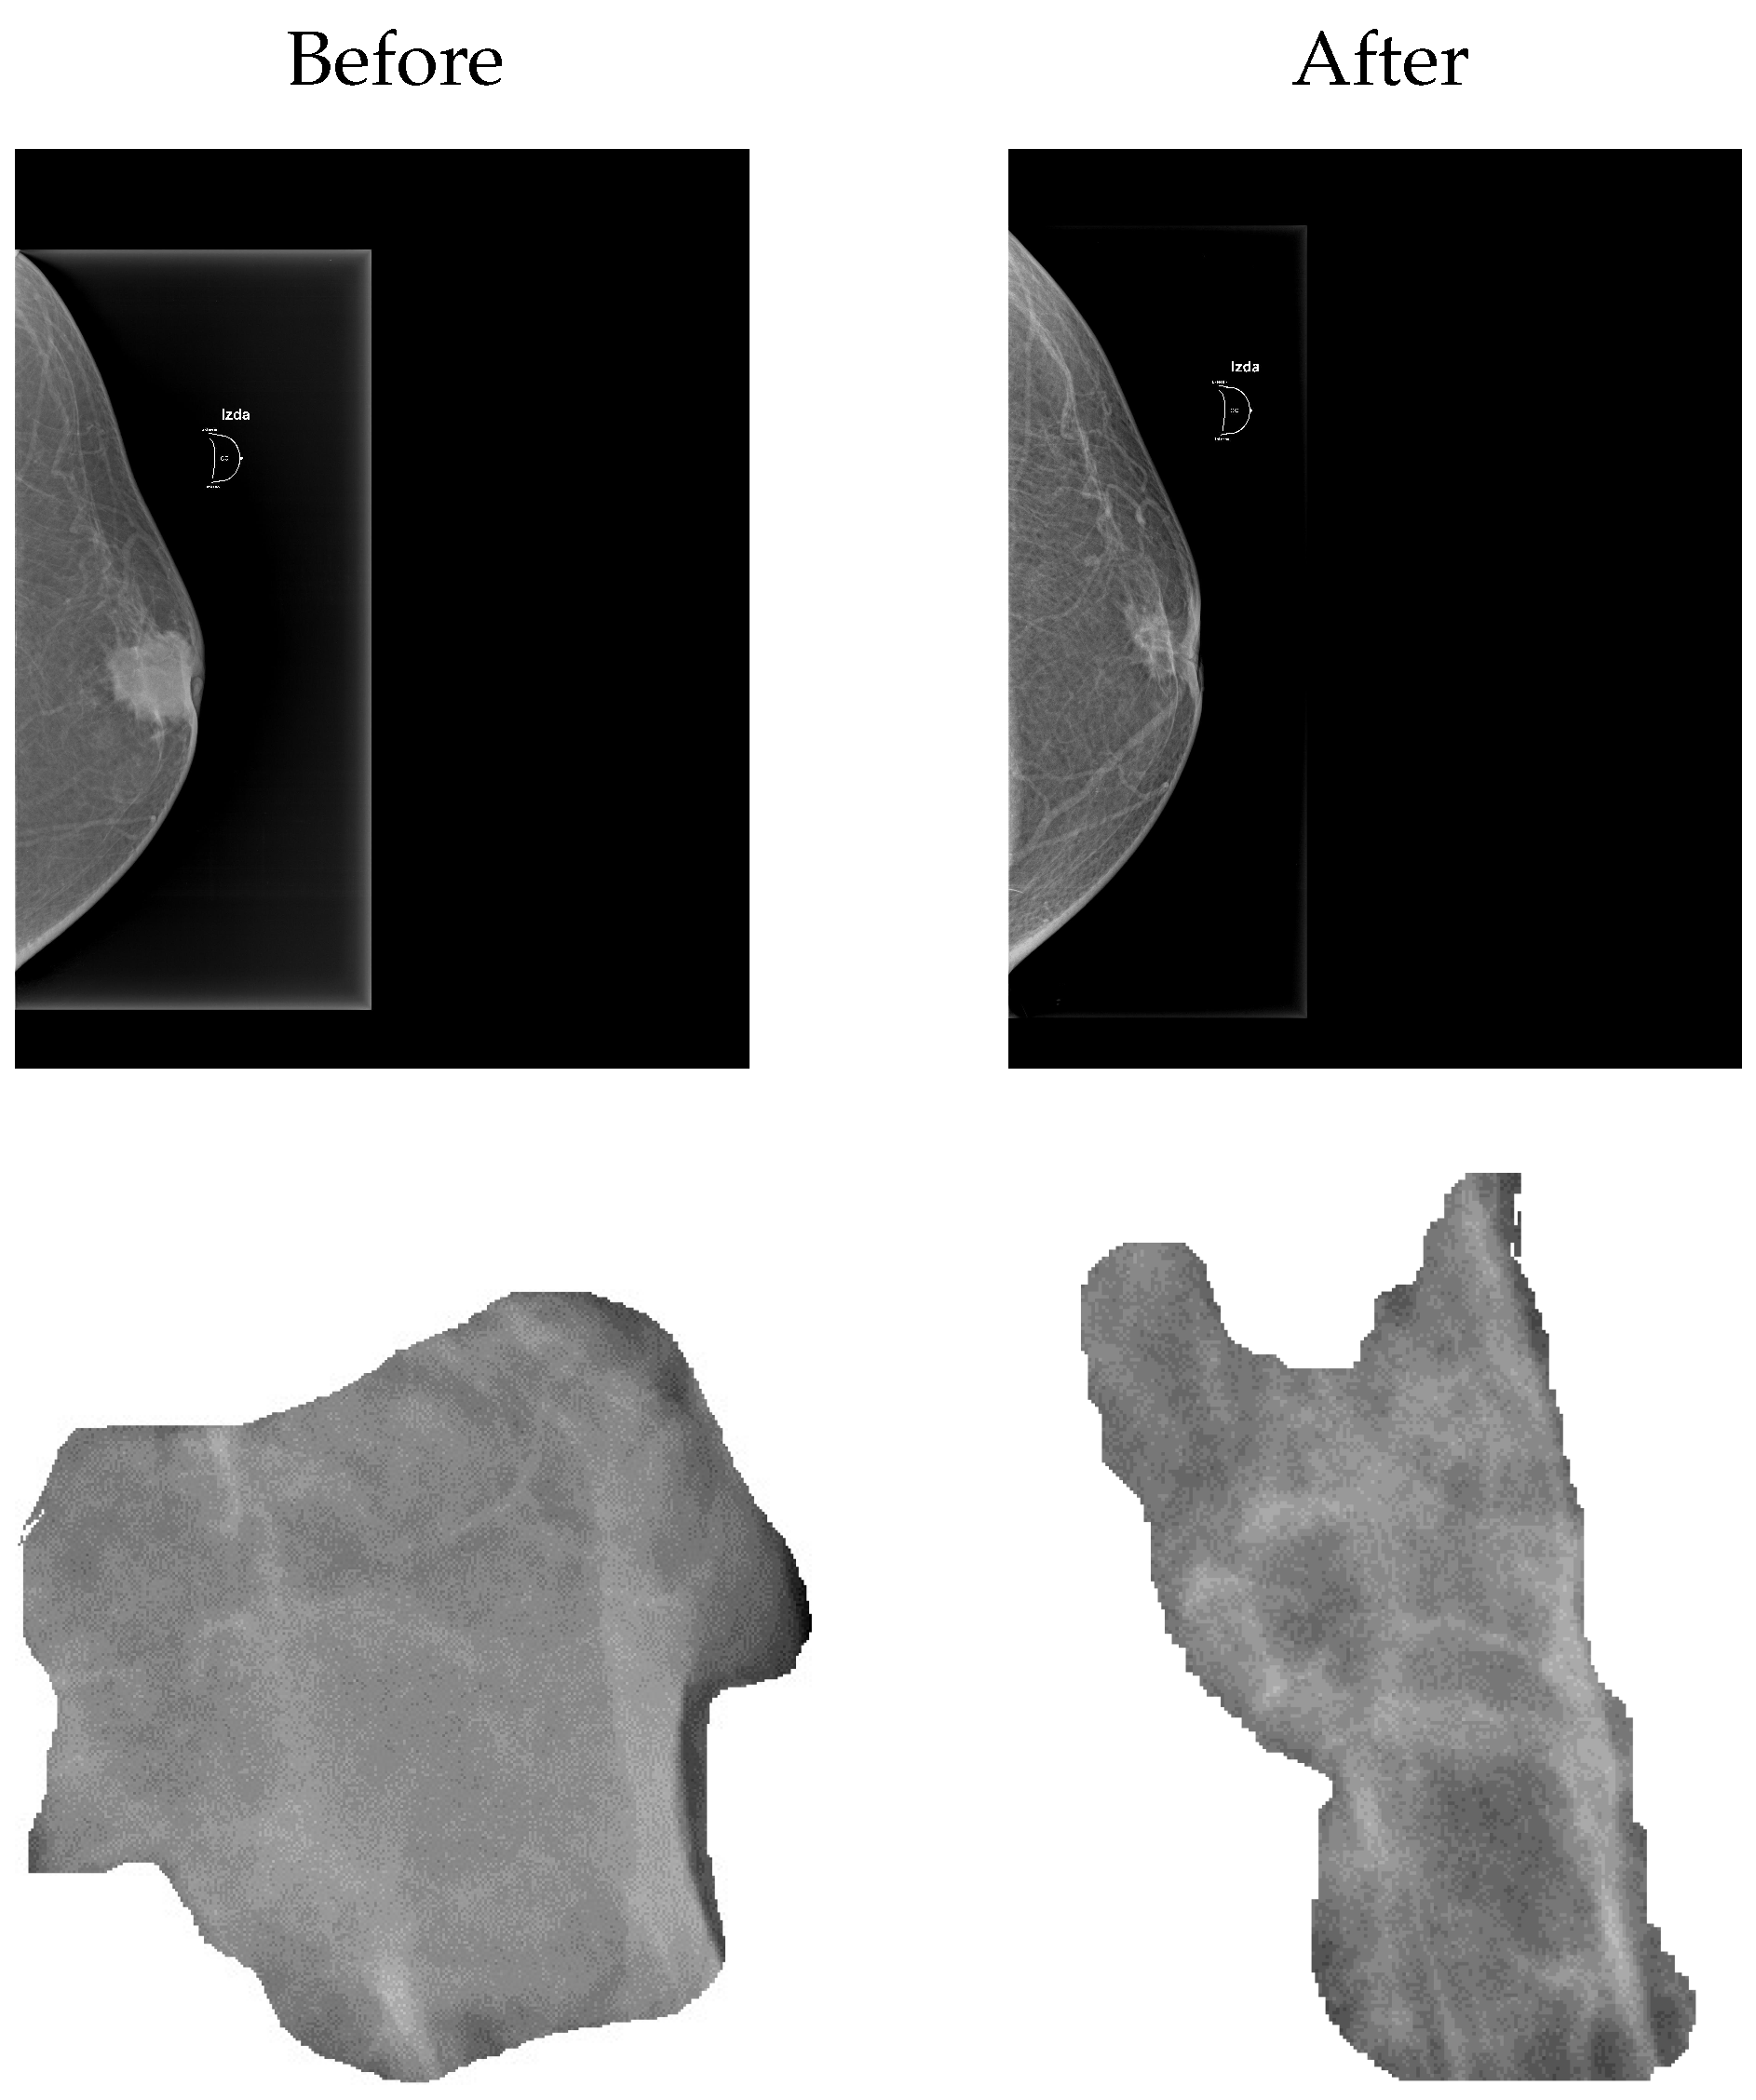

| Study | ADC* | ADC* | MDC* |

|---|---|---|---|

| Before | |||

| After | |||